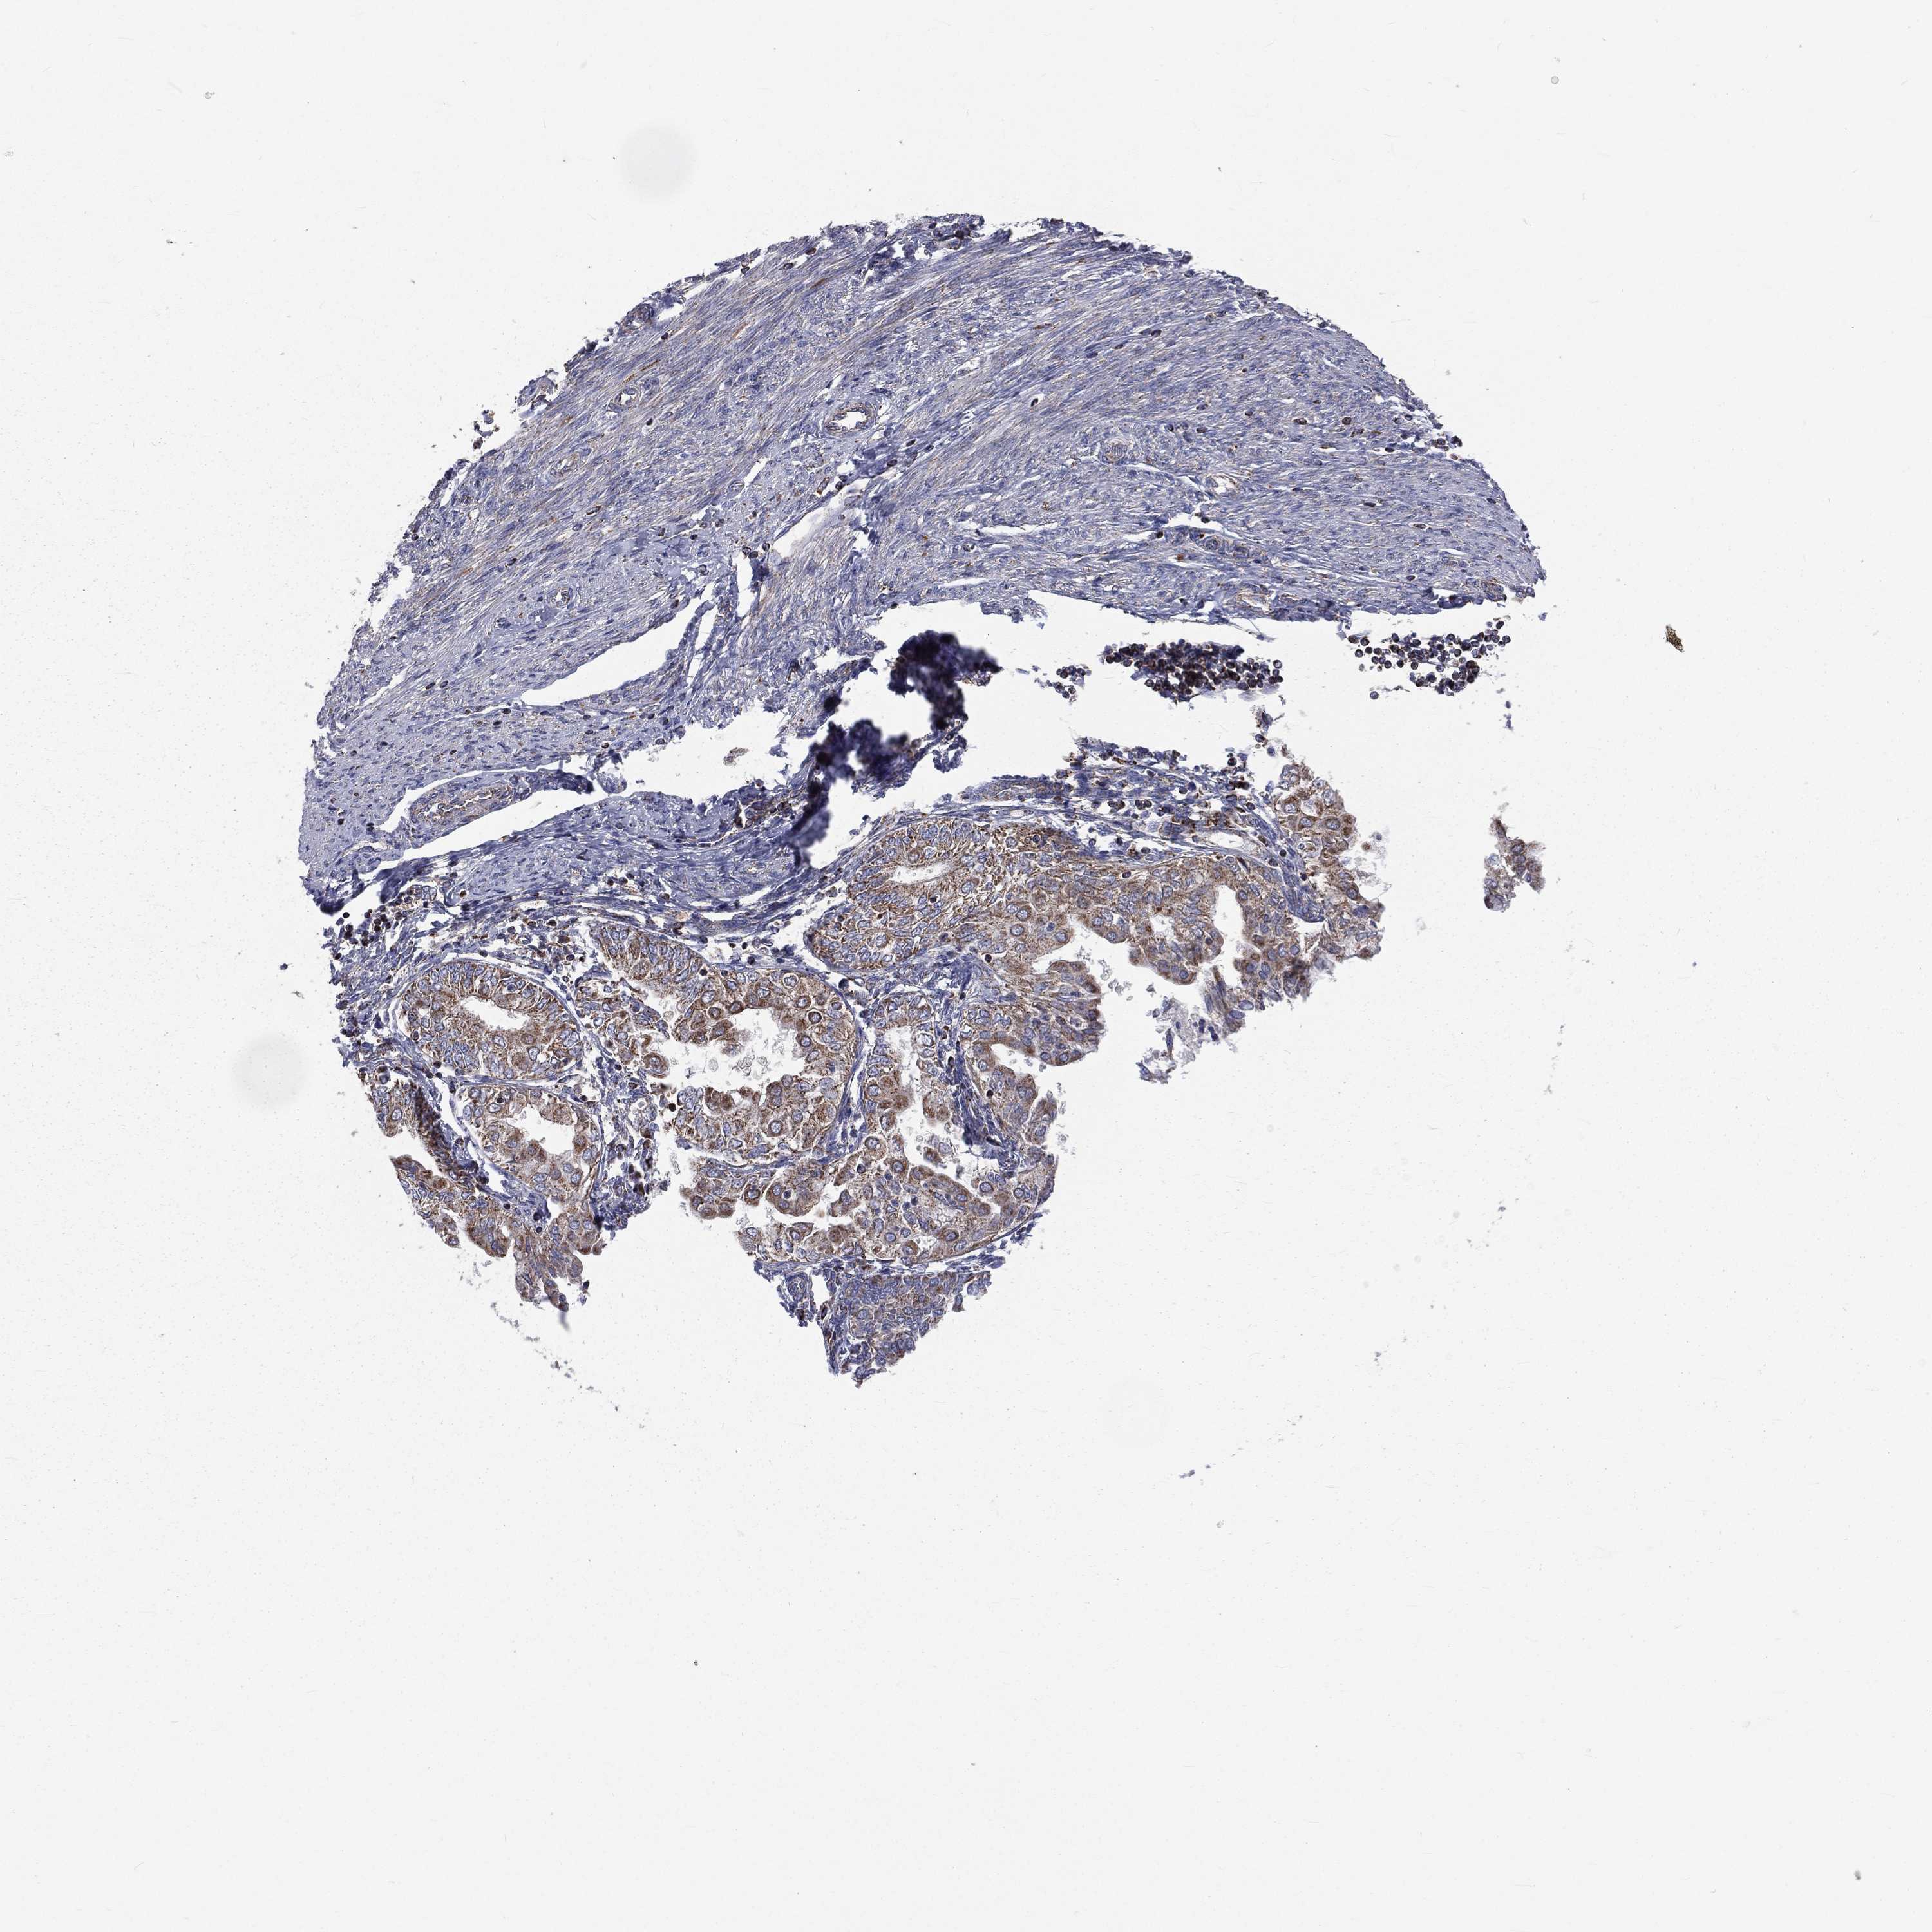

ENDOMETRIAL CANCER - Protein expressioni

A mouse-over function shows sample information and annotation data. Click on an image to view it in a full screen mode. Samples can be filtered based on level of antibody staining by selecting one or several of the following categories: high, medium, low and not detected. The assay and annotation is described here.

Note that samples used for immunohistochemistry by the Human Protein Atlas do not correspond to samples in the TCGA dataset.

Antibody stainingi

Antibody staining in the annotated cell types in the current human tissue is reported as not detected, low, medium, or high, based on conventional immunohistochemistry profiling in selected tissues. This score is based on the combination of the staining intensity and fraction of stained cells.

Each image is clickable and will lead to virtual microscopy that enables deeper exploration of all samples and also displays staining intensity scores, fraction scores and subcellular localization as well as patient and tissue information for each sample.

Antibody HPA044620

Antibody HPA058621

Staining

High

Medium

Low

Not detected

Intensity

Strong

Moderate

Weak

Negative

Quantity

>75%

75%-25%

<25%

None

Location

Nuclear

Cytoplasmic/membranous

Cytoplasmic/membranous,nuclear

Adenocarcinoma, NOS